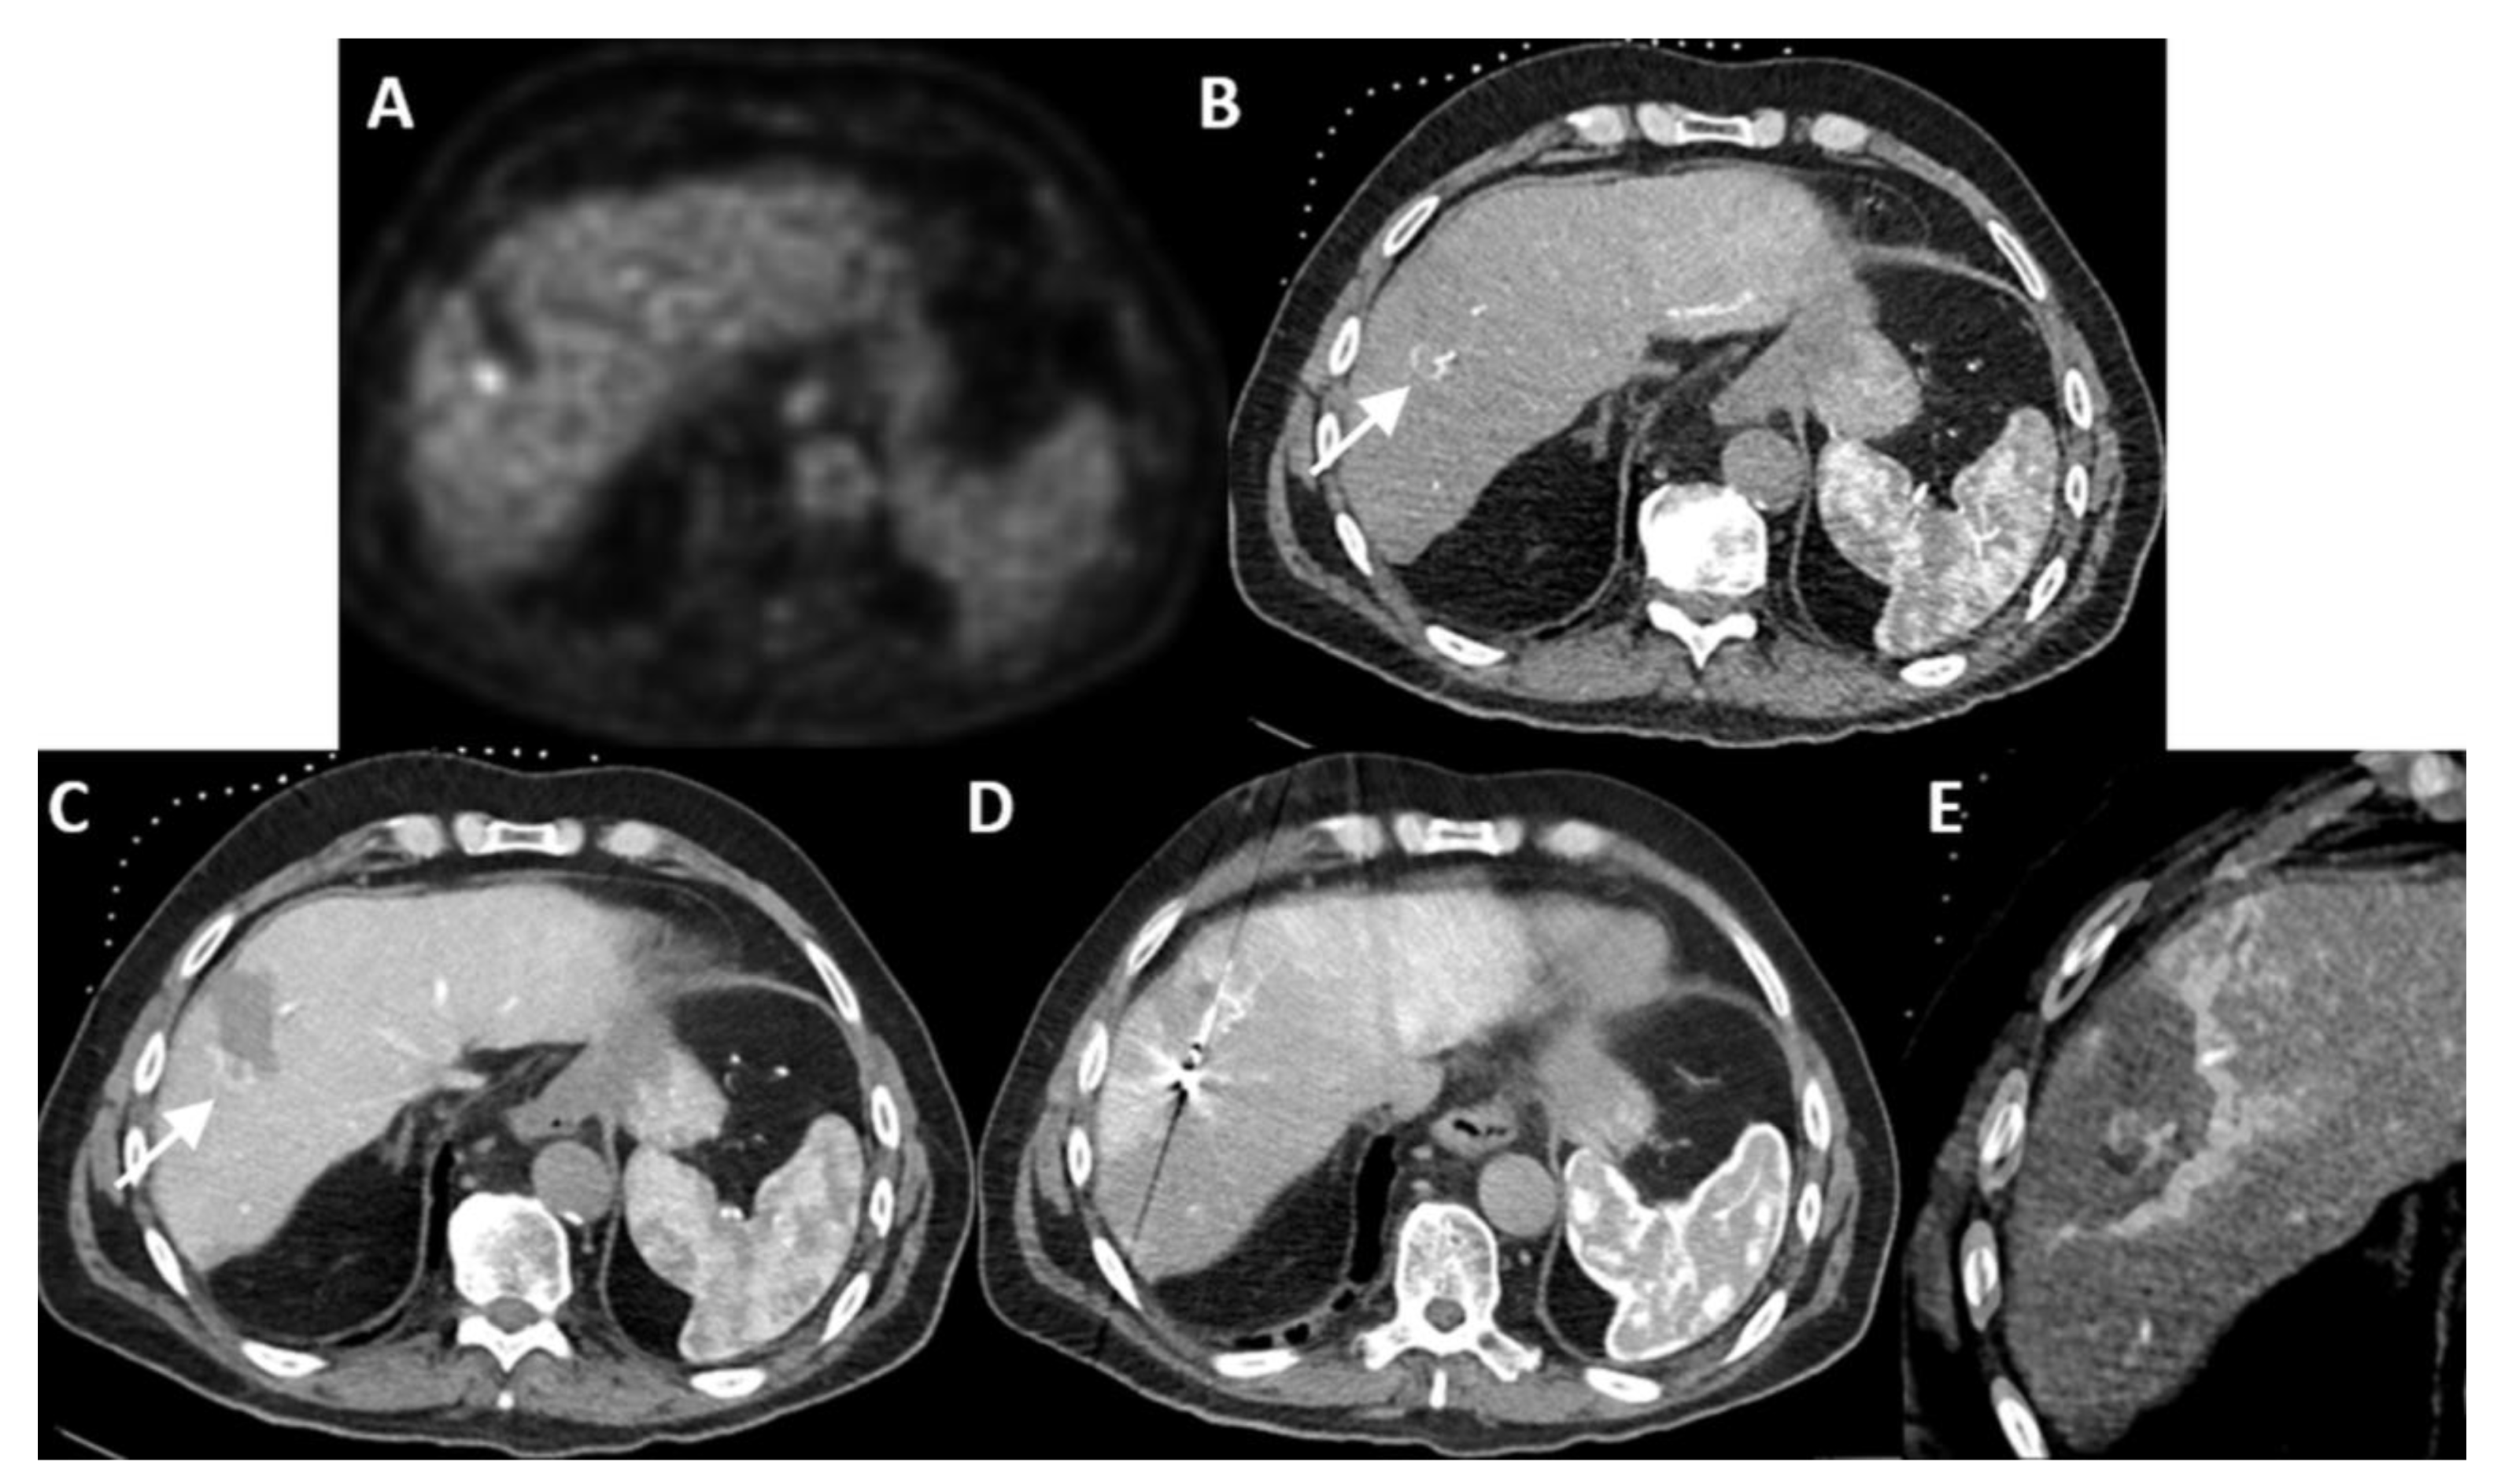

| Case No. | Tumor Size (mm) | Catheter Tip Position | Amount and Type of Contrast per Injection | Ablation Device | Institute |

|---|---|---|---|---|---|

| 1 | 20 mm | Common hepatic artery | 15–20 mL Visipaque™ | Emprint™ Microwave Ablation System, Medtronic-Covidien, Boulder, CO, USA | MD Anderson, Houston, TX, USA |

| 2 | 20 and 7 mm | Common hepatic artery | 4 mL Xenetix 300® | Cool-tip™ RFA Ablation Aystem, Medtronic-Covidien, Boulder, CO, USA | Gustave Roussy, Villejuif, France |

| 3 | 12 mm | Left-sided hepatic artery | Not specified | Cool-tip™ RFA Ablation System | Gustave Roussy |

| 4 | 9 mm | Common hepatic artery | 10 mL Xenetix 300® | Emprint™ Microwave Ablation System | Amsterdam UMC, Amsterdam, The Netherlands |

| 5 | 15 mm | Coeliac trunk | 20 mL Xenetix 300® | Emprint™ Microwave Ablation System | Amsterdam UMC |

| 6 | Not applicable | Common hepatic artery | 20 mL Xenetix 300® | Emprint™ Microwave Ablation System | Amsterdam UMC |

| 7 | Confluent | Common hepatic artery | 10 mL Xenetix 300® | NanoKnife system under ECG-gating; AccuSync model 72, AngioDynamics, Latham, NY, USA | Amsterdam UMC |

| 8 | 15 mm | Common hepatic artery | 15–20 mL Visipaque™ | Emprint™ Microwave Ablation System | MD Anderson |